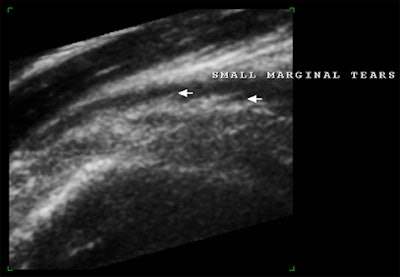

![]() |

| Above and below, post-traumatic multiplanar and enlarged 3D reconstruction of the supraspinatus tendon with small marginal tears that were better depicted using 3D reconstruction. |